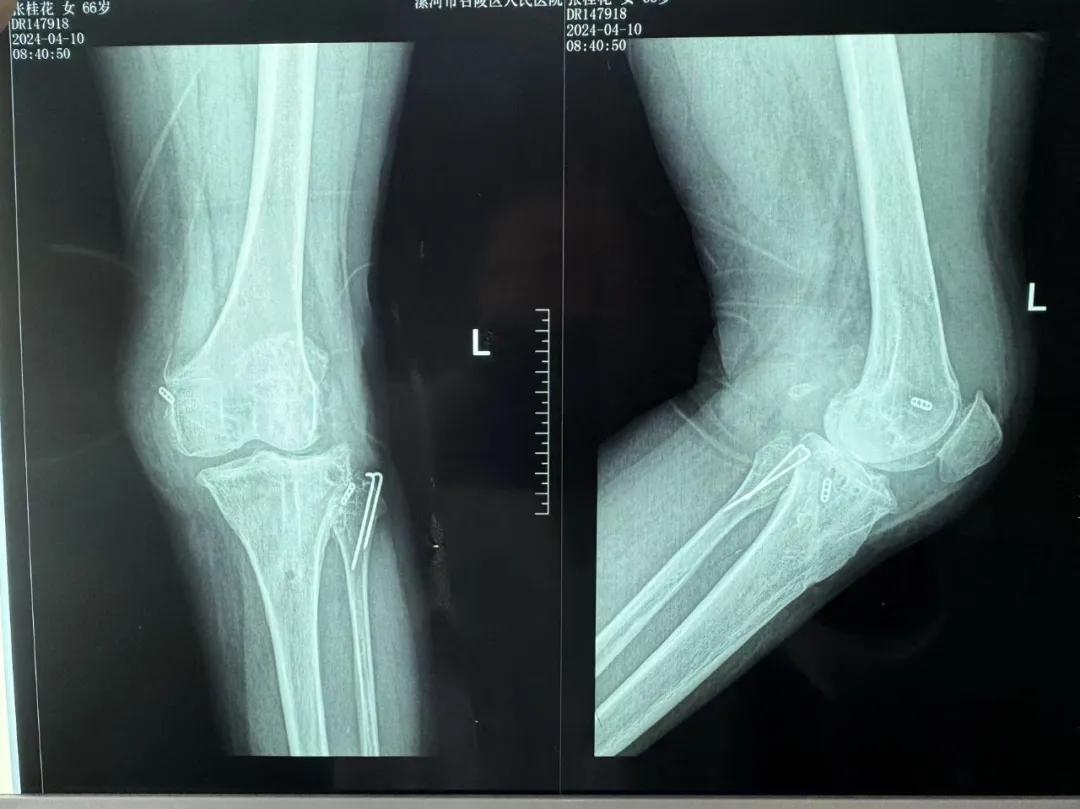

患者來院后,漯河市骨科醫(yī)院(漯河醫(yī)專二附院、漯河市立醫(yī)院)主治醫(yī)師康樂便成了她的管床醫(yī)生。在經(jīng)過詳細(xì)的術(shù)前診斷與檢查后,關(guān)節(jié)外科主任李付彬組織科室團(tuán)隊針對患者的診斷情況進(jìn)行術(shù)前討論——患者為重度膝關(guān)節(jié)骨關(guān)節(jié)炎,需進(jìn)行人工關(guān)節(jié)置換。但術(shù)前的評估結(jié)果顯示:患者膝關(guān)節(jié)側(cè)方不穩(wěn)定,單純行初次表面膝關(guān)節(jié)置換,術(shù)后仍會存在側(cè)方不穩(wěn)的情況,會影響術(shù)后效果以及假體使用年限,不僅無法完全恢復(fù)膝關(guān)節(jié)功能,還會加重患者的經(jīng)濟(jì)負(fù)擔(dān)。

為了盡可能給患者帶來更好的治療效果,減輕其經(jīng)濟(jì)負(fù)擔(dān),經(jīng)綜合評估后,李付彬主任帶領(lǐng)團(tuán)隊制定了最終的手術(shù)方案——決定使用髁限制性膝關(guān)節(jié)假體(LCCK)置換膝關(guān)節(jié)。作為解決患者病痛的最優(yōu)方案,這項手術(shù)具體實施的難度并不小,需要在術(shù)中根據(jù)截骨情況進(jìn)行多次評估和實時調(diào)整,這就要求主刀醫(yī)生不僅要具備過硬的專業(yè)技術(shù)與能力,還要能夠結(jié)合自身的經(jīng)驗準(zhǔn)確判斷、精準(zhǔn)操作。

手術(shù)過程中,關(guān)節(jié)外科團(tuán)隊為患者進(jìn)行了標(biāo)準(zhǔn)截骨,經(jīng)過評估,患者膝關(guān)節(jié)仍存在膝關(guān)節(jié)側(cè)方不穩(wěn)定,便按照原定手術(shù)計劃使用LCCK假體進(jìn)行了膝關(guān)節(jié)置換。經(jīng)過再次評估,患者膝關(guān)節(jié)穩(wěn)定性恢復(fù),下肢力線正常,這臺高難度的LCCK膝關(guān)節(jié)置換手術(shù)在一小時內(nèi)便順利完成!術(shù)后第二天,患者就能夠自主下床負(fù)重活動,功能恢復(fù)良好。